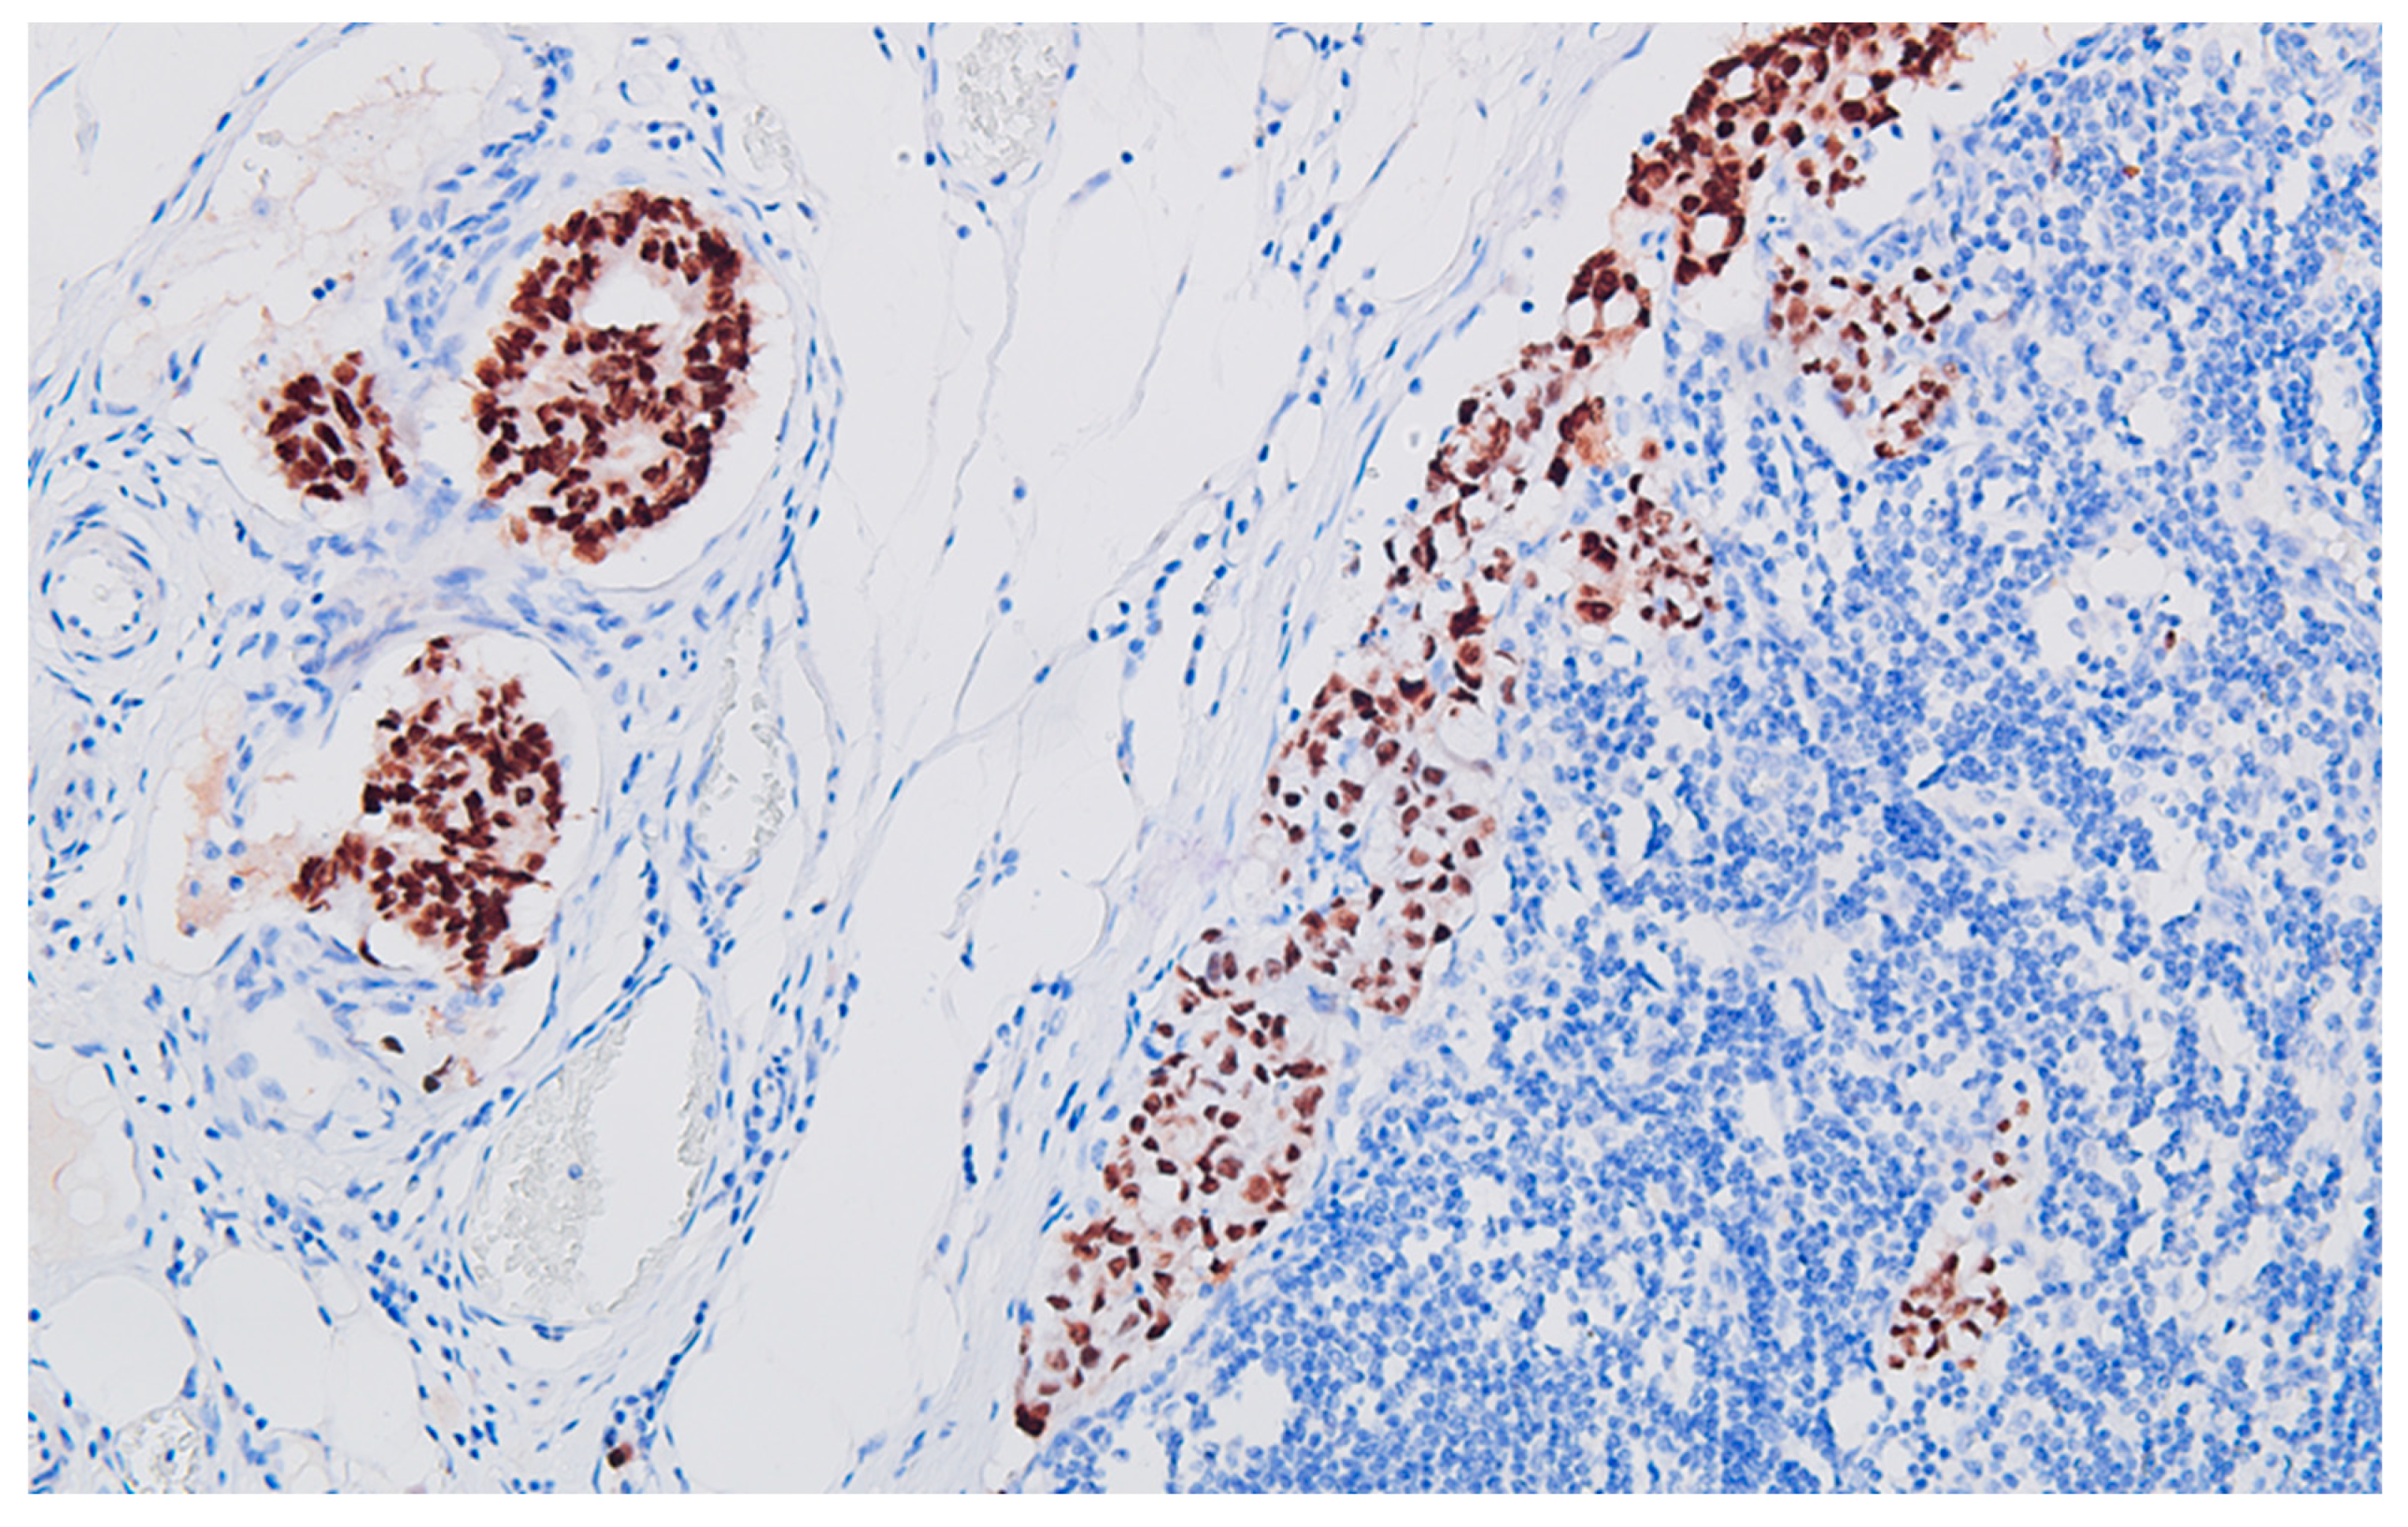

Figure 5. Regional lymph node metastasis of the colon carcinoma, with adenocarcinoma pattern, CK20 heterogeneous / patchy positive, DAB x200.

The immunohistochemical profile of the carcinoma CK7 negative, patchy CK20 positive (Figure 5), diffuse CDX2 positive (Figure 6), corresponds to a primary colorectal carcinoma, and for the peritoneal tumor nodules the diffuse S100 protein positivity (Figure 7), patchy CD68 positive (Figure 8), together with CD117 (c-kit) negative reaction, leads to the diagnosis of granular cell tumor / granular cell nerve sheath tumor / Abrikossoff tumor and exclude a possible association of a gastrointestinal stromal tumor with the colonic carcinoma.